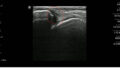

三角靱帯(DL)の損傷所見

・距骨が外側にずれることがある

・内側のクリアスペースの拡大

・内側が3mmを超える広がりは病的とされる